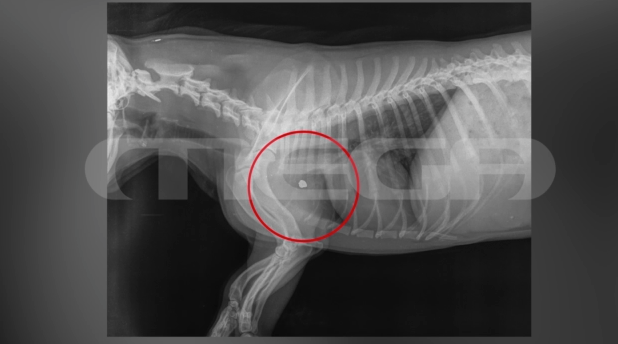

Ο σκύλος, μάλιστα, που ακούγεται να σπαράζει στο βίντεο μετά τον πυροβολισμό, ανήκε σε γειτόνισσα του φερόμενου ως δράστη και επέστρεψε τραυματισμένος στην ιδιοκτήτριά του. Η ακτινογραφία που έγινε στο σκυλί, όταν η ιδιοκτήτρια το πήγε στην κτηνίατρο, έδειξε τη σφαίρα καρφωμένη κοντά στο μπροστινό του πόδι.

Ο Χρήστος Ευαγγέλου, αντιδήμαρχος κοινωφελών δομών και ποιότητας ζωής, είπε στην εκπομπή «Live News»: «Η κτηνίατρος μας ενημέρωσε ότι το σκυλί δεν κινδυνεύει σοβαρά. Είναι αγχωμένο, συγχυσμένο. Είναι δύσκολο να βγει η σφαίρα από το σώμα του ζώου. Η σφαίρα είναι κάτι που χρειάζεται η αστυνομία για την έρευνά της».

«Ήξερε που πυροβολούσε, πυροβόλησε κοντά στην καρδιά. Η βολίδα αυτή τρύπησε το ζώο και για δύο εκατοστά δεν έφτασε κοντά στην καρδιά. Δεν μπορεί να γίνει χειρουργείο, η βολίδα έμεινε μέσα και ο σκύλος επιστράφηκε στην ιδιοκτήτρια», πρόσθεσε ο Ζήκος Νικόλαος.